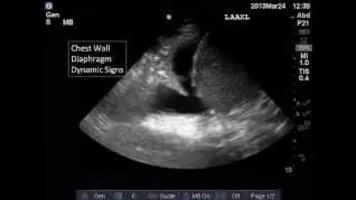

Chest Sonography photograph

Chest Sonography

Chest sonography is an established procedure in the stepwise imaging diagnosis of pulmonary and pleural disease. It is the method of choice to distinguish between solid and liquid lesions and allows the investigator to make an unequivocal diagnosis without exposing the patient to costly and stressful procedures. . . .